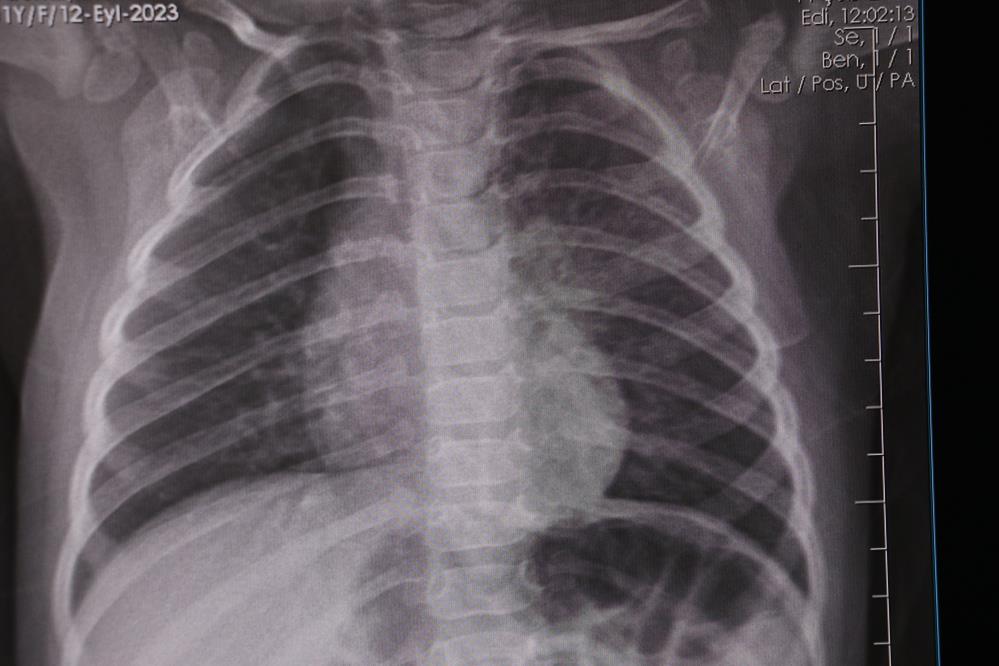

Dr. Tuğçe Uçar, influenzanın her yıl kış mevsiminde daha yaygın hale gelen ve solunum yolu enfeksiyonlarına neden olan bir virüs olduğunu belirterek, "İnfluenza, her yıl kış mevsiminde daha yaygın hale gelen ve solunum yolu enfeksiyonlarına neden olan bir virüstür. Çocuklarda yüksek ateş, öksürük, burun akıntısı, yaygın kas ağrıları, halsizlik ve genel vücut yorgunluğu gibi şikâyetlerle kendini gösteren bir hastalık tablosuna yol açar. Özellikle kreş ve okul çağındaki çocuklarda çok hızlı yayılır. Solunum yoluyla, damlacık enfeksiyonu şeklinde bulaşır. Bu yüzden, ellerin düzenli olarak yıkanması, kalabalık ortamlardan uzak durulması ve hijyen kurallarına dikkat edilmesi büyük önem taşır. Hasta bireyden bulaştıktan sonra belirtiler genellikle ilk 24 saat içinde ortaya çıkmaya başlar. Hastalık ortalama 7-10 gün sürer. Ateşli dönem ise genellikle 5 gün kadar devam edebilir. Öksürük ise birkaç gün içinde başlayıp birkaç haftaya kadar devam edebilir" dedi.

Dr. Uçar, influenza hastalığının kalıcı bir bağışıklık bırakmadığını söyleyerek, "Hastalığın tanısını çoğu zaman kan tahliline gerek kalmadan, burundan alınan sürüntü örnekleri ile koyabiliyoruz. Erken tanı konulursa, hastalığın mümkün olan antiviral tedavisine erken başlayabiliyoruz. Böylelikle gelişebilecek akciğer komplikasyonları gibi ciddi riskleri azaltmış oluyoruz. İnfluenza hastalığı ne yazık ki kalıcı bir bağışıklık bırakmıyor. Domuz gribi, kuş gribi olarak bildiğimiz H1N1 virüsü, çeşitli mutasyonlara uğrayarak her yıl değişik varyantlarla karşımıza çıkıyor. Bu hastalığı bir kere geçirmek bir daha geçirilmeyecek anlamına gelmiyor. Özellikle ekim ve nisan ayları arasında pik yapan bu hastalığın bir aşısı mevcut. İnfluenzadan korunmak için riskli gruplara da aşılanmayı öneriyoruz" diye konuştu.